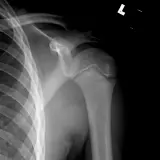

Over 2,100 interactive radiology cases, curated by radiologists for your level of training. Scroll, window, and view cases full screen — just like on PACS. Click linked findings in each writeup to jump straight to them on the image. Cases include sample reports, a focused discussion section, original illustrations, and videos.

完全交互式病例,配备您在 PACS 上期待的各项工具——滚动、调窗、缩放、平移、测量、ROI 和全屏模式。

丰富的标注直接在病例图像上突出关键发现。点击病例讲解中的关联发现,即可跳转至其在扫描上的精确位置。